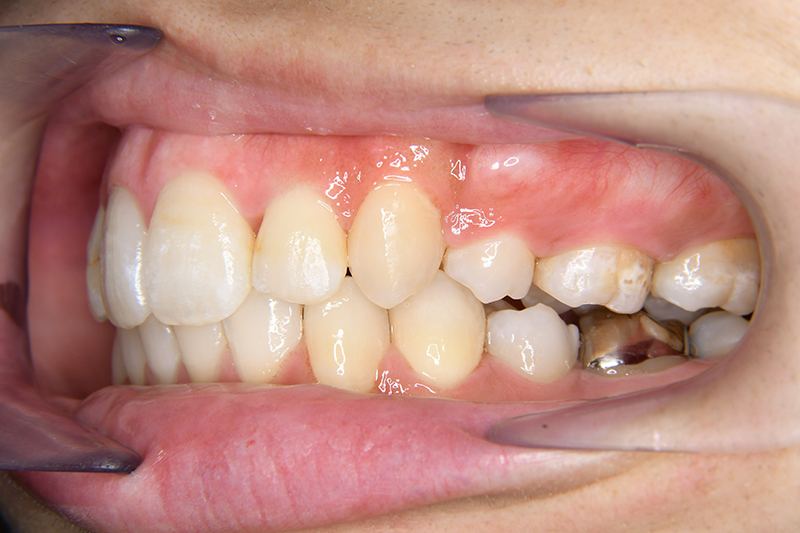

初診時

FP・IOP

口腔内所見 over jet 11.5mm、over bite 5.5mm、右側臼歯関係Full ClassⅡ級、左側end onⅡ級、上顎顎歯列はテーパー型であり、上顎中切歯は押し出されるように大きく唇側傾斜していた。下顎前歯部は叢生を呈しており、左下5は歯冠長が短く半埋伏していた。